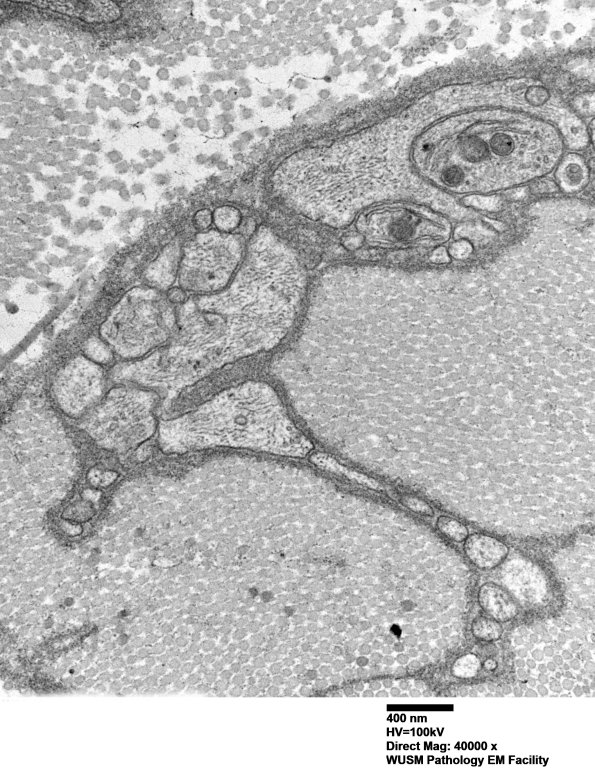

Two magnifications of the edge of the Schwann cell shown in 7A3A. It is difficult to find all Schwannian processes with discernable thick basement membranes. (electron micrographs)